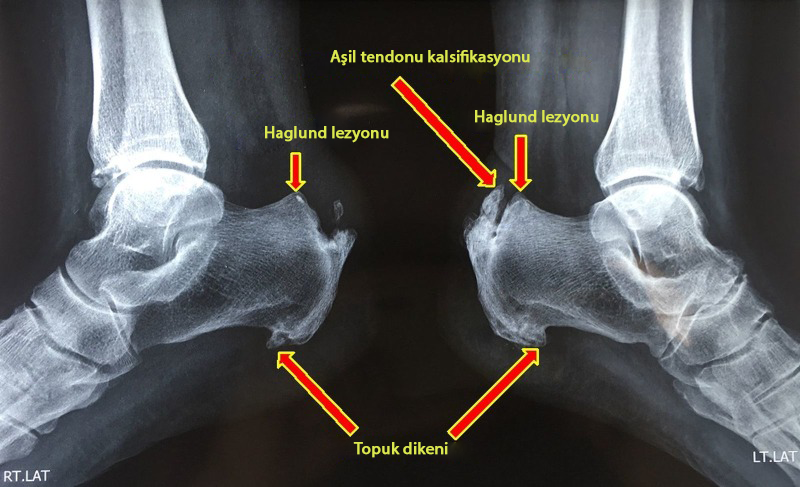

Haglund hastalığının teşhis edilmesi zor olabilir, çünkü semptomlar Aşil tendiniti de dahil olmak üzere diğer ayak sorunlarıyla ilişkili semptomlara benzer. Kemik büyümesinin tam olarak görmek ve ayakta veya ayak bileğinde soruna neden olan başka bir şeyin olup olmadığını görmek için röntgene çekilir.

Haglund lezyonlu hastanın ayak yan grafileri